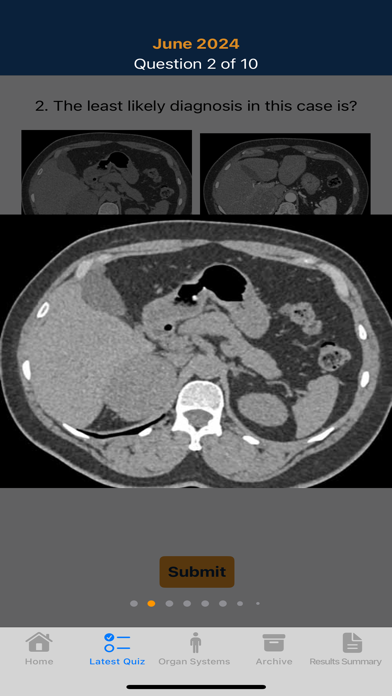

One of the classic formats for learning radiology has always been the quiz.In this application we provide you with our latest innovation in CT education taking advantage of the iPad and iPhone.

It's unique capabilities provide an easy to use environment that combines images , text and sound to enhance the learning experience. Over 1800 cases in 15 different categories that include case specific pearls and an audio discussion of the case.